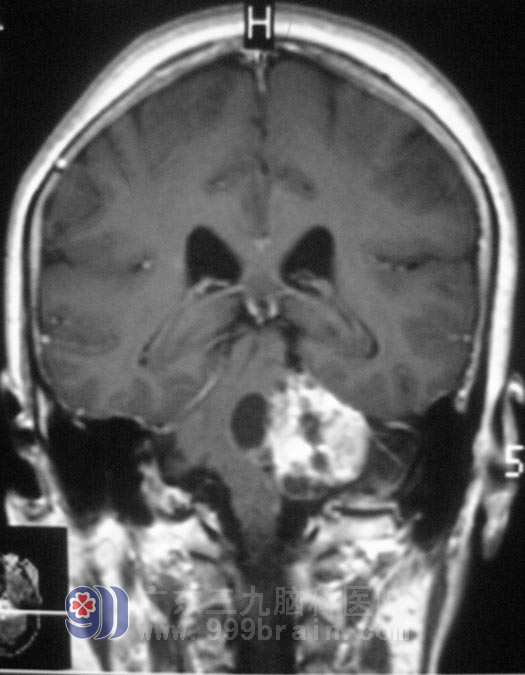

广东三九脑科医院头颅MR检查显示:左侧桥小脑角区示一不规则形囊实性占位性病变,增强后实性部分呈不均匀明显强化,囊性部分未见强化,侧面听神经增粗强化,范围约为3.6cm×4.2cm×3.7cm,周围示轻微水肿,桥脑、延髓,左侧桥臂及左侧小脑半球受压变形、移位,四脑室受压变窄,左侧内听道明显扩大。检查左耳失聪,左侧额纹、鼻唇沟较右侧轻微变浅,伸舌左偏。